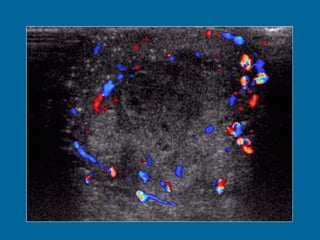

a)  Longitudinal US image of the left testis shows a heterogeneous, predominantly hypoechoic mass, with scattered areas of hypoechogenicity (arrowheads). Normal testicular parenchyma is compressed peripherally by the tumor and contains diffuse microlithiasis (arrow).  (b)  Doppler US image shows normal peripheral vascularity with absence of central flow.

Longitudinal US image of the left testis shows a heterogeneous, predominantly hypoechoic mass, with scattered areas of hypoechogenicity (arrowheads). Normal testicular parenchyma is compressed peripherally by the tumor and contains diffuse microlithiasis (arrow).  (b)  Doppler US image shows normal peripheral vascularity with absence of central flow.

a) LongitudinalUS image of the left testis shows a heterogeneous, predominantly hypoechoic mass, with scattered areas of hypoechogenicity (arrowheads). Normal testicular parenchyma is compressed peripherally by the tumor and contains diffuse microlithiasis (arrow). (b) Doppler US image shows normal peripheral vascularity with absence of central flow.

Longitudinal US imageof the left testis shows a heterogeneous, predominantly hypoechoic mass, with scattered areas of hypoechogenicity (arrowheads). Normal testicular parenchyma is compressed peripherally by the tumor and contains diffuse microlithiasis (arrow). (b) Doppler US image shows normal peripheral vascularity with absence of central flow.